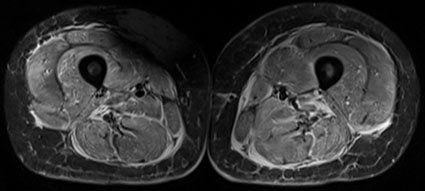

14-jähriges Mädchen mit florider Myositis der Oberschenkelmuskulatur, die sich in beidseits erhöhtem Signal der Muskeln (entsprechend ödematösen Veränderungen) und der Muskelfaszien auf den wassergewichteten, fettunterdrückten (STIR) MR-Aufnahmen zeigt (A).